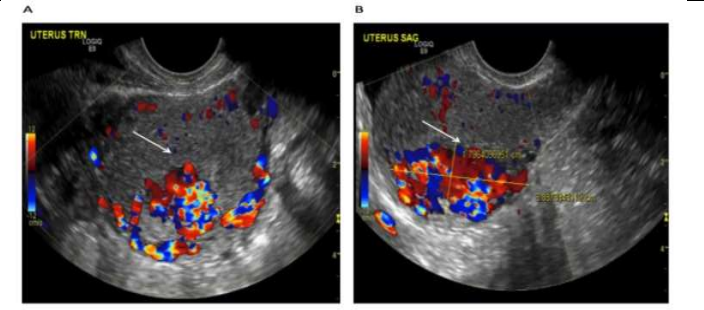

Figure 2: USG-pelvis revealed 8.8 cm x 7.5 cm x 7.5 cm bulky uterus the posterior myometrium markedly enlarged and heterogeneous with increased vascularity on Doppler. Doppler showed PSV of 121 cm / s & RI of 0.36 i.e., high velocity, low resistance flow, ET-14mm in lower uterine segment. Reproduced from: [16] Shintre H S, Coelho K S. Managing Uterine Arteriovenous Malformation (AVM) Is Like Dealing with Raging Wildfire Awaiting A Spark: Better Be Extremely Cautious & Be Ready With Counter Measures Like Uterine Artery Embolization (UAE). Obstet. Gynecol. Int. J. 2017; 6(1): 00195 DOI: 10.15406/ogij:2017.06.00195

https://medcraveonline.com/OGIJ/managing-uterine-arteriovenous-malformation-avm-is-like-dealing-with-raging-wildfire-awaiting-a-spark-better-be-extremely-cautious-amp-be-ready-with-countermeasures-like-uterine-artery-embolization-uae.html under copy right ©2017 Shintre, et al. This is an open access article distributed under the terms of the, which permits unrestricted use, distribution, and build upon your work non-commercially

Shintre and Coelho [16] reported a 27-year-old lady who was known to have Thalassemia minor who had manifested with heavy vaginal bleeding and passage of clots over the preceding two days. She stated that she had been having continuous on and off mild to moderate vaginal bleeding pursuant to a second trimester therapeutic abortion she had undergone two months preceding her presentation. She did undergo therapeutic abortion in view of the fact that she had her chorionic venous samples which had shown that the foetus had Thalassemia major due to the fact that both herself and her husband had Thalassemia minor. The therapeutic abortion was induced with utilization of misoprostol (PGE1) tablets. The reports of the obstetrician who undertook the therapeutic abortion did document that the abortion was complete and therefore no curettage was undertaken pursuant to her abortion. She had also undergone another therapeutic abortion 8 months earlier for the same reason following chorionic villous sampling that showed Thalassemia major foetus. This therapeutic abortion was ensued by curettage of her uterine cavity for complete evacuation of her products of conception. She did not have any significant past medical or surgical history. She was noted to be pale or otherwise her general examination was normal. She had speculum examination of her vagina which showed a partially open cervical os that associated with minimal blood clots. There was no active bleeding. Her uterus was bulky, and it measured about 8 weeks to 10 weeks size as well as it was firm to soft in consistency, firm to soft with regard to consistency, mobile and associated with free fornices. The results of some of his laboratory blood tests included: Haemoglobin 9.5 grams per decilitre, platelets 3-lakhs, Serum Beta Human Chorionic Gonadotrophin (B-HCG) 35 MIU/ML which was normal, normal coagulation screen and normal liver function tests. Her blood sample was sent for grouping and saving for future use when required. She had ultrasound scan and magnetic resonance imaging (MRI) of pelvis. The MRI scan demonstrated a bulky uterus that measured 4 cm x 7 cm x 7 cm, heterogeneous lesion within the posterior wall of her uterus, lost endometrial-myometrial interface, multiple dilated tortuous blood vessels within her posterior myometrium which had suggested the likelihood of retained products of conception or gestational trophoblastic tumour which would represent placental site trophoblastic tumour, or uterine vascular malformation (see figure 1). The trans-abdominal ultrasound scan of pelvis did demonstrate an 8.8 cm x 7.5 cm x 7.5 cm bulky uterus the posterior myometrium that was very enlarged as well as heterogeneous with increased vascularity upon Doppler ultrasound scanning (see figure 2). Doppler ultrasound scanning did demonstrate a peak systolic velocity (PSV) of 121 cm / s as well as restrictive index of 0.36. The ultrasound scan also demonstrated that her endometrium was thickened within the lower uterine segment that was suggestive of retained products of conception. She had a chest x-ray which was normal. She had ultrasound scan-guided evacuation of her retained products of conception from her lower uterine segment which was sent for pathology examination. The evacuation of the products of conception did trigger active bleeding. She therefore underwent uterine artery embolization with utilization of cyanoacrylate (glue) (see figure 3). There was no evidence of active bleeding pursuant to her embolization. She was discharged on the 3rd post-procedure op day on oral antibiotics and haematinics. Pathology examination of the tissue did show degenerated and necrosed bits of decidua as well as few degenerate chorionic villi that were admixed with fibrin and blood. The degenerate products of conception did not show pathology examination features of placental site tumour trophoblastic. At her 6-weeks follow-up assessment she stated that her vaginal bleeding had diminished gradually over a period of 4 weeks and the bleeding stopped completely after 4 weeks. She had ultrasound scan of her pelvis with Doppler scan which did show diminished size of the arteriovenous fistula and with diminished vascularity (see figure 4). Shintre et al. [16] stated that the first case of AVM of the uterus was reported in 1926. [17]

Khan et al. [24] reported a 30-year-old G1P0010 lady wo had manifested with a 6 days history of abnormal bleeding from her uterus. Three months preceding her presentation, she had undergone a therapeutic abortion which was ensued by dilatation and curettage (D&C) for retained products of conception. Since then, she realised that she had developed a new onset of menorrhagia, which on the day of her manifestation had become persistent and which had become associated with severe pain, weakness, as well as dizziness. Upon her examination, she was observed to be hypotensive, and she had tachycardia. She had marked tenderness within her supa-pubic region. Her examination was otherwise normal. Some of the results of her laboratory blood tests included: haemoglobin 9.2 grams per decilitre, haematocrit 27.5% and negative serum Beta Human Chorionic Gonadotrophin (B-HCG). She trans-vaginal ultrasound scan which showed a 3.9 cm x 2.7 cm x 1.8 cm sized an-echogenic cystic spaces within the posterior wall of the fundus of her uterus (see figure 8). She had Doppler ultrasound scanning which revealed marked vascularity within her uterus (see figure 9). She had magnetic resonance imaging (MRI) scan of pelvis which showed a contrast-opacified structure within structure within the wall of her myometrium. Focal serpiginous flow voids were also demonstrated within the posterior-superior myometrium with extension to the canal of her myometrium (see figure 10). The features of the radiology were interpreted to be consistent with the diagnosis of arteriovenous malformation of the uterus (AVMU). She had uterine angiogram which confirmed features of arteriovenous malformation of the uterus (AVMU) within the posterior-superior wall of the uterus (see figure 11). The angiogram did demonstrate presence of multiple feeding arteries which had arisen mainly from the left with smaller arteries from the right side. Embolization of both uterine arteries was undertaken with utilization of Gelfoam (Pfizer, New York) pledgets to near stasis. She had a post-embolization arteriogram which demonstrated complete embolization of the AVMU as well as evidence of slow flow of contrast in both uterine arteries. No immediate complications emanated. Her vaginal bleeding stopped. She was discharged home on her 3rd day post-embolization. During her follow-up assessment, 3 weeks pursuant to her embolization there was no evidence of recurrence of abnormal uterine bleeding. The lesson that has been learnt from this case report is that embolization of the uterine artery supplying the AVMU is an effective minimally invasion option of treating AVMUs.

Figure 9:Trans vaginal ultrasound of the uterus with Doppler revealing a hyper-vascular lesion: (A) transverse view (B) sagittal view. Reproduced from: [24] Khan S, Saud S, Khan I, Achakzai B. Acquired Uterine Arteriovenous Malformation Following Dilatation and Curettage Treated with Bilateral Uterine Artery Embolization: A Case Report. Cureus. 2019 Mar 13;11(3):e4250. doi: 10.7759/cureus.4250. PMID: 31131173; PMCID: PMC6516630. https://pubmed.ncbi.nlm.nih.gov/31131173/ under Copyright © 2019, Khan et al. This is an open access article distributed under the terms of the Creative Commons Attribution License, which permits unrestricted use, distribution, and reproduction in any medium, provided the original author and source are credited.